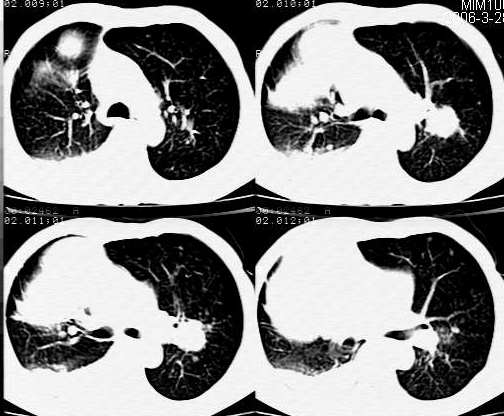

男,68岁,胸部胀痛数年,胸部x光片显示右侧胸腔巨大占位。

ct:右肺巨大肿块、有点、片、环形钙化,内侧达心包膜外侧达胸壁,支气血管受压后移,左下肺见小结节,右侧胸腔积液,纵隔未见肿大淋巴结。

诊断:右肺恶性肿瘤?穿刺活检

一定位肺部:肿块与胸壁、纵隔成锐角,肿块与胸壁纵隔有分界,定位肺部应该是明确的。

二定性:很难明确,考虑肿块大+胸腔积液+左下肺小结节+68岁考虑恶性可能大肉瘤>肺ca

鉴别1纵膈肿瘤2良性肿瘤;如错沟瘤等